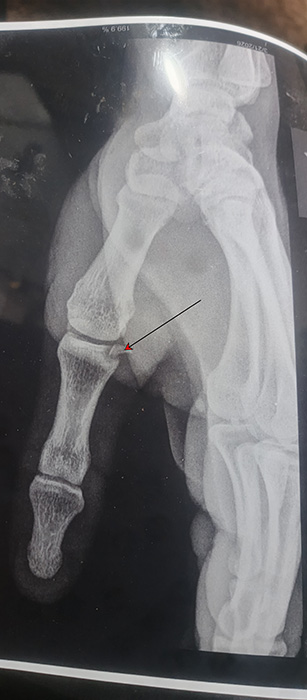

الكسر في قاعدة عظمة السلامي الأولى للإبهام (السهم).

وهو كسر قطعة من العظم متحركة عن موضعها وعادة بعد مرور شهران يكون الكسر قد إلتئم وأعتقد هذه الأشعة اُخذت بيوم الحادثة. المهم الألم يخف بعد مرور هذا الوقت أو بعد 3 أشهر.

ويمكن يكون هناك بعض التيبس بالإصبع وألم خفيف مع الحركة. لا يوجد شيء لعمله أو الحاجة لعمل شيء الآن إلا إذا فيه عدم القدرة أو تحييد في حركة الإبهام.